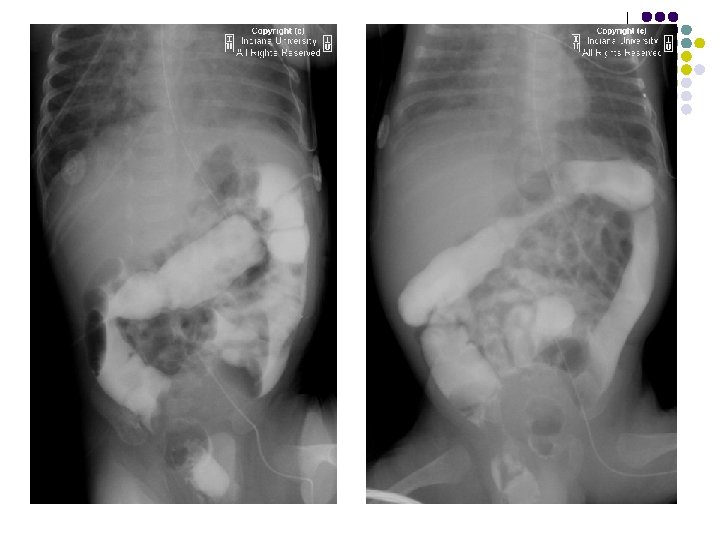

IMAGING FEATURES l Plain abdominal film: A well-defined right lower quadrant mass. l Contrast enema: Smooth indentation of the medial aspect of the cecum & non-opacification of the appendix. l Ultrasound: Completely anechoic or hypoechoic with variable internal echogenicity and Whorled appearance is characteristics due to internal contents May have posterior acoustic enhancement. with variable wall thickness and calcification.

FINDINGS l Supine AP radiograph of the abdomen reveals a normal abundant bowel gas pattern with no evidence of obstruction. l However, gas is seen within a small bowel loop in the right inguinal region. l Delayed supine AP images of the abdomen from a small bowel series demonstrates contrast within a small bowel loop within the right hemiscrotum.

RADIOLOGICAL FEATURES: ON PLAIN RADIOGRAPH: l A loop of air filled bowel will be seen outside the expected location of the abdomen/pelvis. l Occasionally, bowel will be visualized within the scrotum. l Further imaging is usually not needed. SMALL BOWEL FOLLOW THROUGH: l Contrast within a small bowel loop in the right inguinal canal. l Ultrasound is the imaging modality of choice in adults. A loop of bowel demonstrating peristalsis within the inguinal canal is diagnostic. The exam is performed at rest and with the valsalva maneuver in order to diagnose easily reducible hernias.